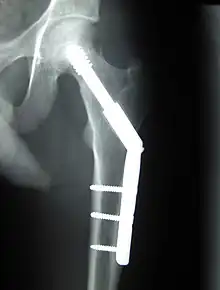

- Chirurgie orthopédique

- Prothèses articulaires (hanche, coude, genou, poignet…)  Une prothèse de genou. Une prothèse de genou.

- Réparation de fractures (vis, plaques, clous, broches)

- Prothèses articulaires (hanche, coude, genou, poignet…)